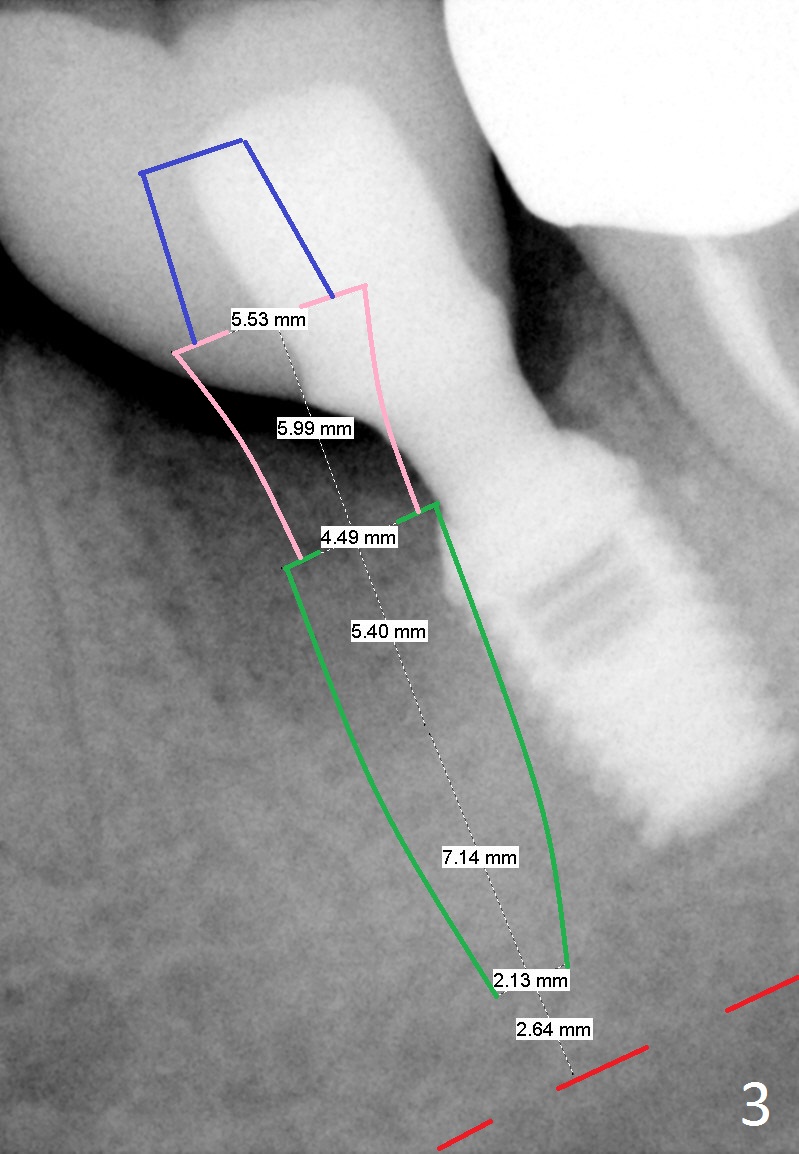

A 42-year-old woman presented to clinic 11 years ago with history of extraction of the tooth #19 two months earlier (Fig.1).  Two months later, a 5x8 mm Bicon implant was placed (Fig.2).  Integrated Abutment Crown was delivered 2 years later (Fig.3) with persistent radiolucency in the mesial socket.  The tooth #18 was extracted with socket preservation 7 years ago.  Recently she returned with chief complaint of chewing pain in the lower left for a while.  The buccal gingiva of #19 is erythematous, edematous and tender (Fig.4).  There are healing abutment at #29 and implant crown at #30.